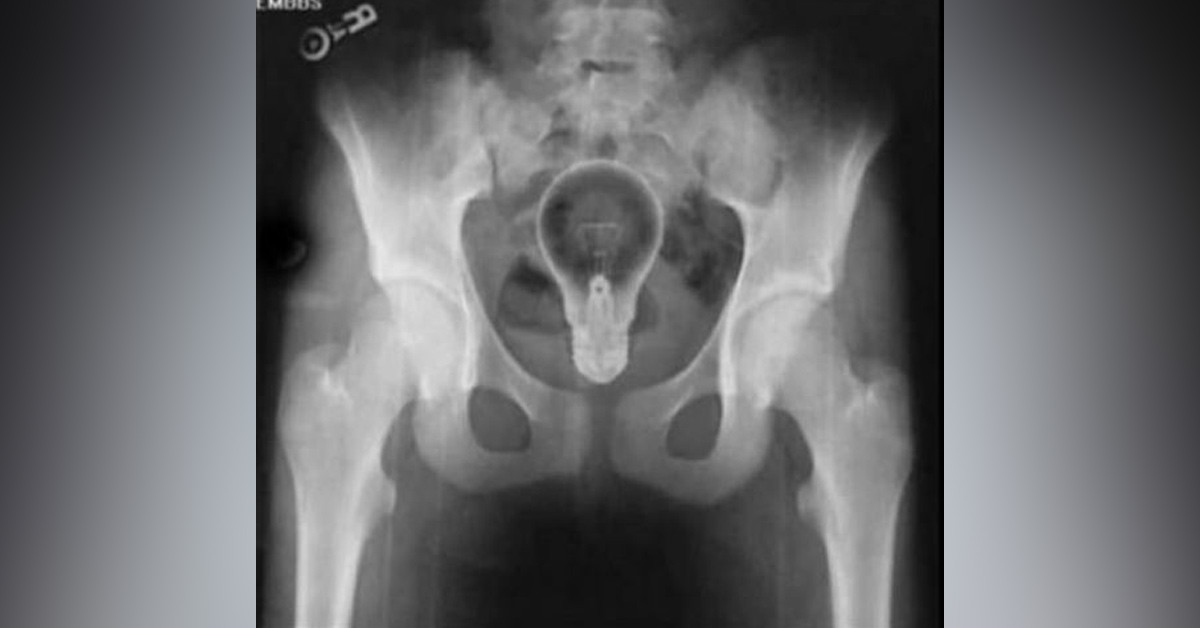

Günümüzde bazı rahatsızlıklarda kişiler çarelerini modern tıpta bulamıyor. Hal böyle olunca farklı yollara başvurabiliyor. Tabi böyle durumlarda ilginç sonuçlar ortaya çıkabiliyor. Örneğin geçen günlerde Şanlıurfa'da basur problemini çözmek için hacamat yaptıran adamın başına akıllara durgunluk getiren bir şey geldi. Hacamat yaptırdıktan 1 hafta sonra anüs bölgesinde ağrıları baş edilemez bir hale gelince hastaneye başvurdu. Adamın röntgen filminde çıkan görüntü ise ''pes'' dedirtti!

Şanlıurfa'da basur problemi sebebiyle hacamat yaptıran adam, bir hafta geçtikten sonra anüs bölgesinde rahatsızlık hissetti. Çekilen röntgen filminde anüs bölgesinde çay bardağı görüldü. Bardak ameliyatla çıkarıldı.